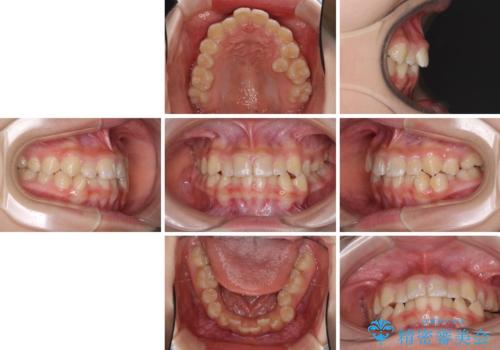

- 小児矯正の頃から診察を行っている患者様です。

上顎骨の幅が下顎骨よりも小さいので、拡大装置により骨幅を広げて上下関係を改善し、その後インビザラインにて歯並びを整えることとしました。

上下の骨幅を改善したことで、スムーズに歯列矯正を行うことができました。

インビザライン治療開始直後に遠方に引っ越しをされたため、通院間隔が長くなり、治療期間が長くなりましたが、しっかりと治療を行うことができました。